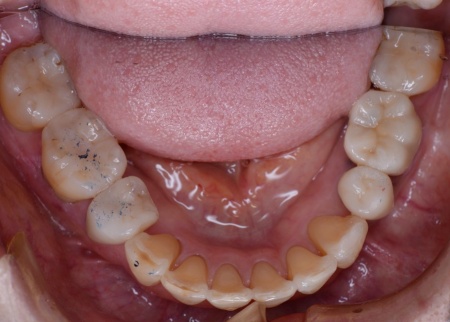

60代女性 すきっ歯が目立つ噛み合わせをワイヤー矯正とアライナー矯正の併用で改善した症例

「以前矯正治療を行ったが、気付いたら前歯がすきっ歯になっていた」とご相談いただきました。

拝見したところ、前歯に隙間が空いており、いわゆるすきっ歯の状態でした。

すきっ歯は見た目の問題だけでなく、食べ物が詰まりやすくなり虫歯や歯周病のリスクが高まる、発音がしにくくなる、噛み合わせが悪化して消化器官や顎関節への負担が増えるなどのおそれがあります。

このまま放置すると、口腔内の環境が悪化して最終的に歯を失いかねないため、早めの治療が必要だと診断しました。